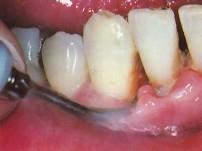

使用超声波洁牙机时,工作头应与牙面成 ( ) A.20度角左右 B.10度角左右 C.80度角左右 D.25度角左右 E.15度角左右

问题 使用超声波洁牙机时,工作头应与牙面成 ( )

选项 A.20度角左右 B.10度角左右 C.80度角左右 D.25度角左右 E.15度角左右

答案 E